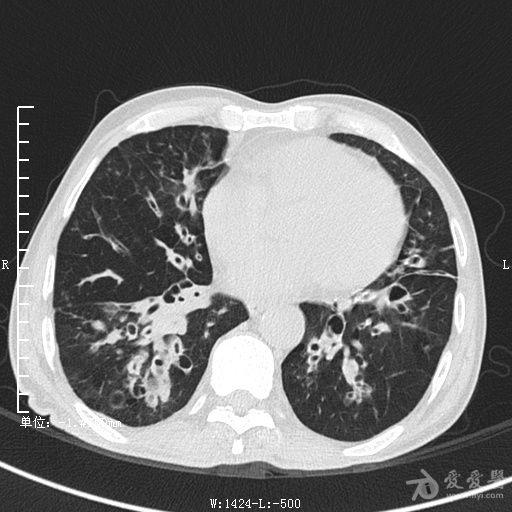

典型支气管扩张及肺水肿CT片

典型支气管扩张肺水肿